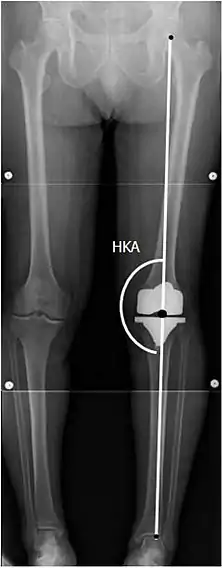

Knee replacement is routinely evaluated by X-ray, including the following measures:

HKA: Hip-knee-ankle angle, which is ideally between 3° varum to 3° valgum from a right angle.[60]

- FFC: frontal femoral component angle. It is typically regarded as optimal when being 2–7° in valgus.[61]

- FTC: frontal tibial component angle, which is regarded as optimal when being at a right angle. A varus position of more than 3° has generally been found to increase the failure rate of the prosthesis.[61]

- Anterior femoral notching (the femoral component causing reduced thickness of the distal femur anteriorly), seems to cause an increased risk of fractures when exceeding about 3 mm.[62]

- LTC: lateral (or sagittal) tibial component angle, which is ideally positioned so that the tibia is 0–7° flexed compared to at a right angle with the tibial plate.[61]